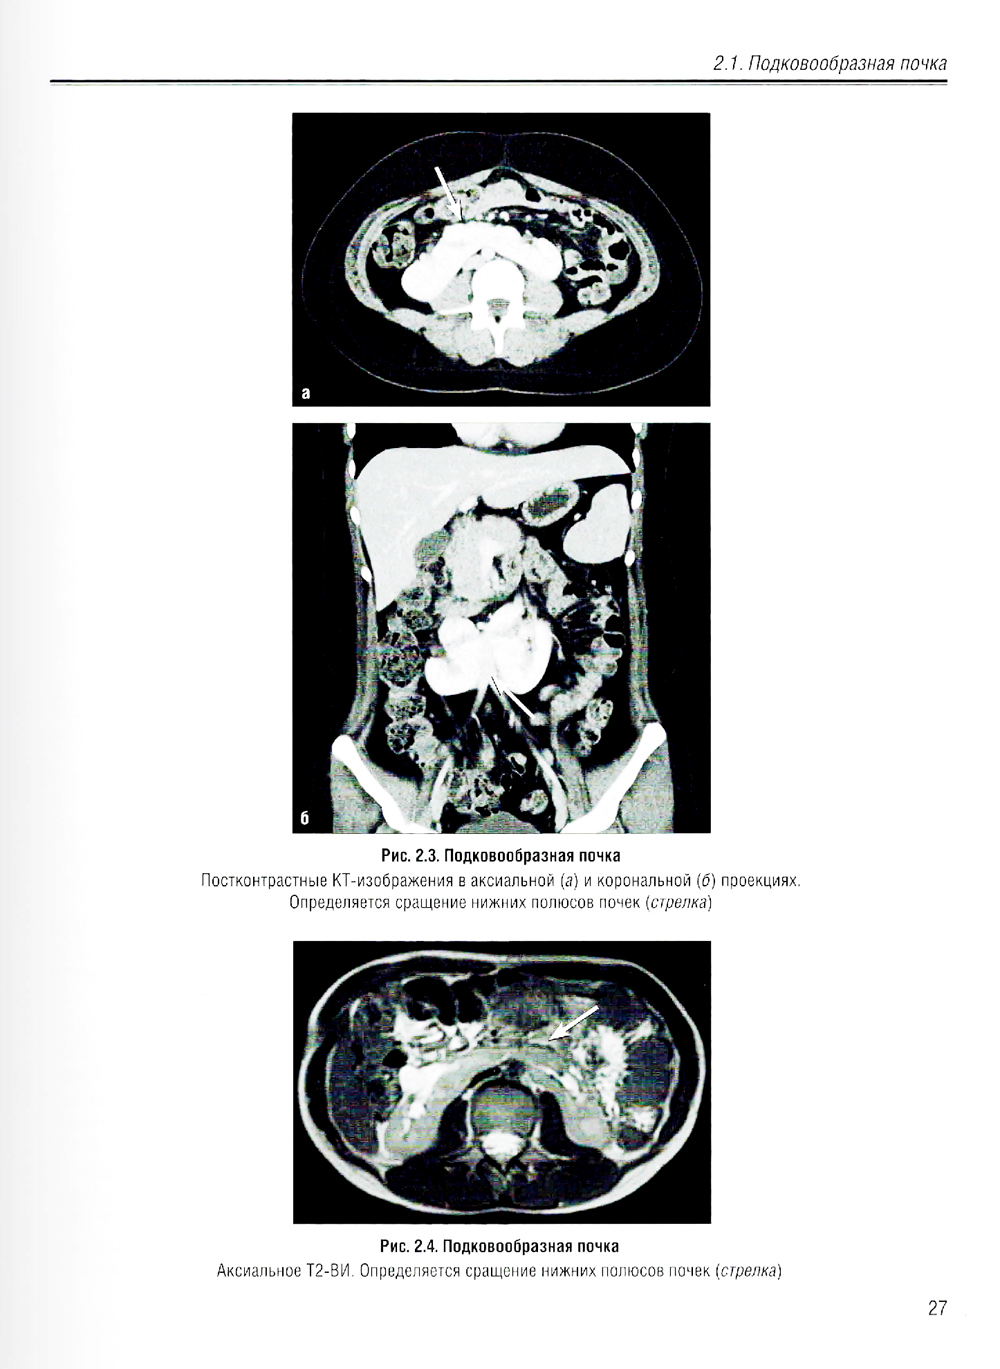

В учебном пособии изложена нормальная лучевая анатомия почек, мочеточников и мочевого пузыря по данным рентгенологического исследования, КТ, МРТ и УЗИ. Приведено описание лучевой семиотики наиболее часто встречающихся заболеваний и повреждений почек, мочеточников и мочевого пузыря с представлением данных УЗИ, КТ и МРТ. Даются рекомендации по тактике лучевого исследования, приводится дифференциальная диагностика. Рассматриваются вопросы этиологии, патогенеза, морфологии и клинические проявления заболеваний. Предназначено для ординаторов, обучающихся по специальностям: 31.08.08 - «Радиология»; 31.08.09 - «Рентгенология»; 31.08.11 - «Ультразвуковая диагностика», а также врачей смежных специальностей. Учебное пособие может быть рекомендовано для подготовки в системе непрерывного медицинского образования.| Издательство | Элби |